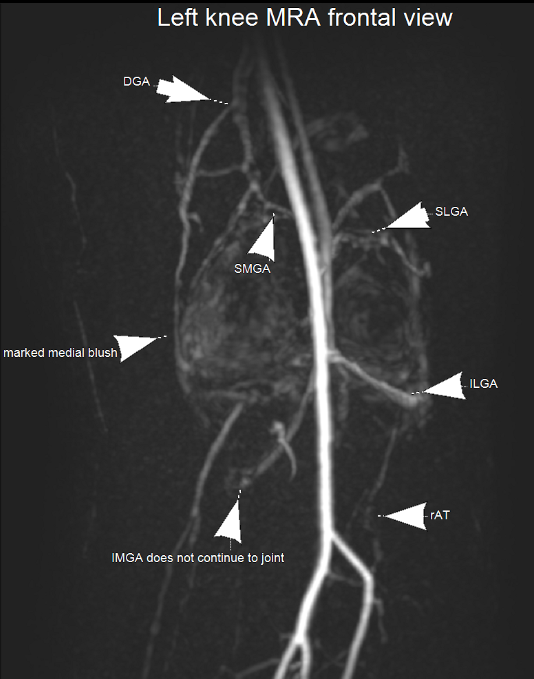

MRI angiography shows the genicular arteries supplying the knee and associated hypervascularity on the medial side. This hypervascularity is caused by neo-vessels as a result of inflammation, with further neo-nerves growing in and causing pain.

MRI knee with a post gadolinium T1FS sequence showing marked enhancement of the knee joint affecting the synovium with a small effusion. The hypervascularity demonstrated here is associated with neo-nerve growth, resulting in severe pain.

MR angiography showing the genicular arteries of the knee.

MRI demonstrates marked synovial hyperenhancement in a patient with knee osteoarthritis. A great target for TAME.